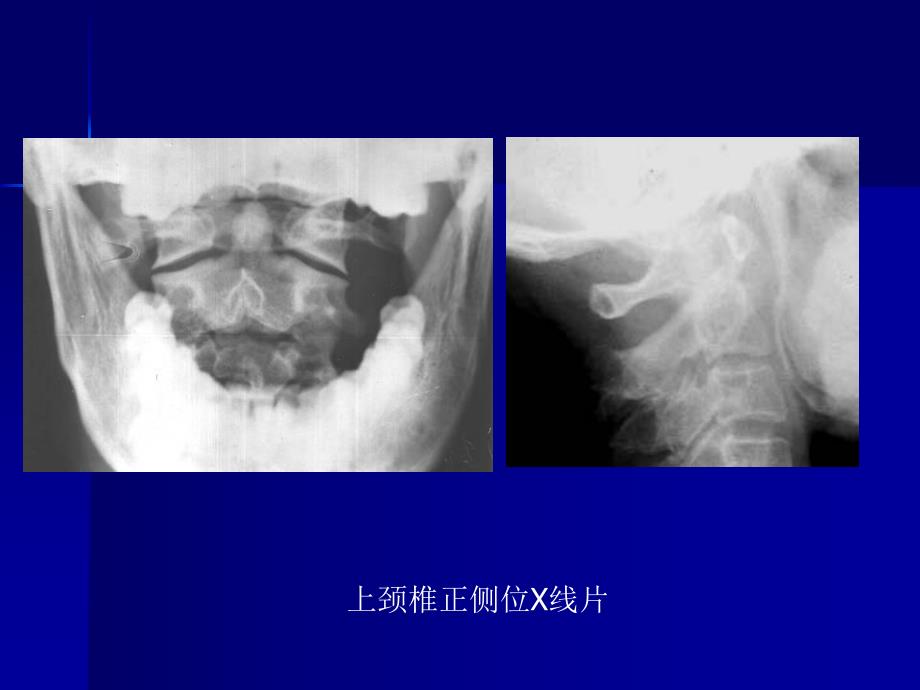

脊柱外科影像学检查脊柱外科影像学检查正常脊柱的影像学检查正常脊柱的影像学检查上颈椎正侧位X线片颈椎正侧位颈椎斜位X线片颈椎MRI常见疾病的影像学检查常见疾病的影像学检查寰椎枕骨化、颅底凹陷症游离齿突畸形C12半脱位伴颈椎椎管内占位类风湿关节炎导致C12半脱位脊髓空洞症颈椎分节不全伴脊髓型颈椎病脊髓型颈椎病脊髓型颈椎病OPLLHangman骨折颈椎骨折胸椎黄韧带骨化症颈椎损伤致颈髓T2加权高信号胸椎黄韧带骨化症LDHLDHL23结核腰3椎体骨折腰45滑脱胸2半椎体畸形腰3椎体血管瘤腰椎椎管造影L1椎体转移性肿瘤Cobbs角测量脊柱旋转程度分级椎体角和椎间盘角咽后间隙和气管后间隙椎体间活动度测量颈椎椎管矢状径测量谢谢 谢谢 大大 家家!